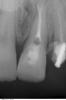

Мaxim Опубликовано 27 апреля, 2013 Поделиться Опубликовано 27 апреля, 2013 Уважаемые коллеги, подскажите как бы кто поступил в данной ситуации:21 наружняя резорбция, в канале цемент, при попытке ревизии выскочили в резорбцию, инструмент заклинил и остался. В канале Vitapex, последние 2 мм не пройдены.У нас варианта 2:1.Пломбировка альфа-гуттой, хирургическим путем извлечь инструмент, MTA, остеопластический материал и под наблюдение.2..Пломбировка альфа-гуттой, резекция,MTA, остеопластический материал и под наблюдение.Снимки. Прикрепленные изображения Ссылка на комментарий